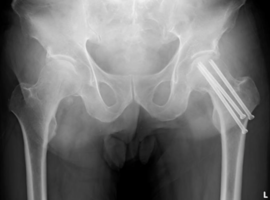

Screw Exchange Technique Following Internal Fixation Failure in a Displaced Femoral Neck Fracture: A Case Report

Volume 4, Issue 4

Read More